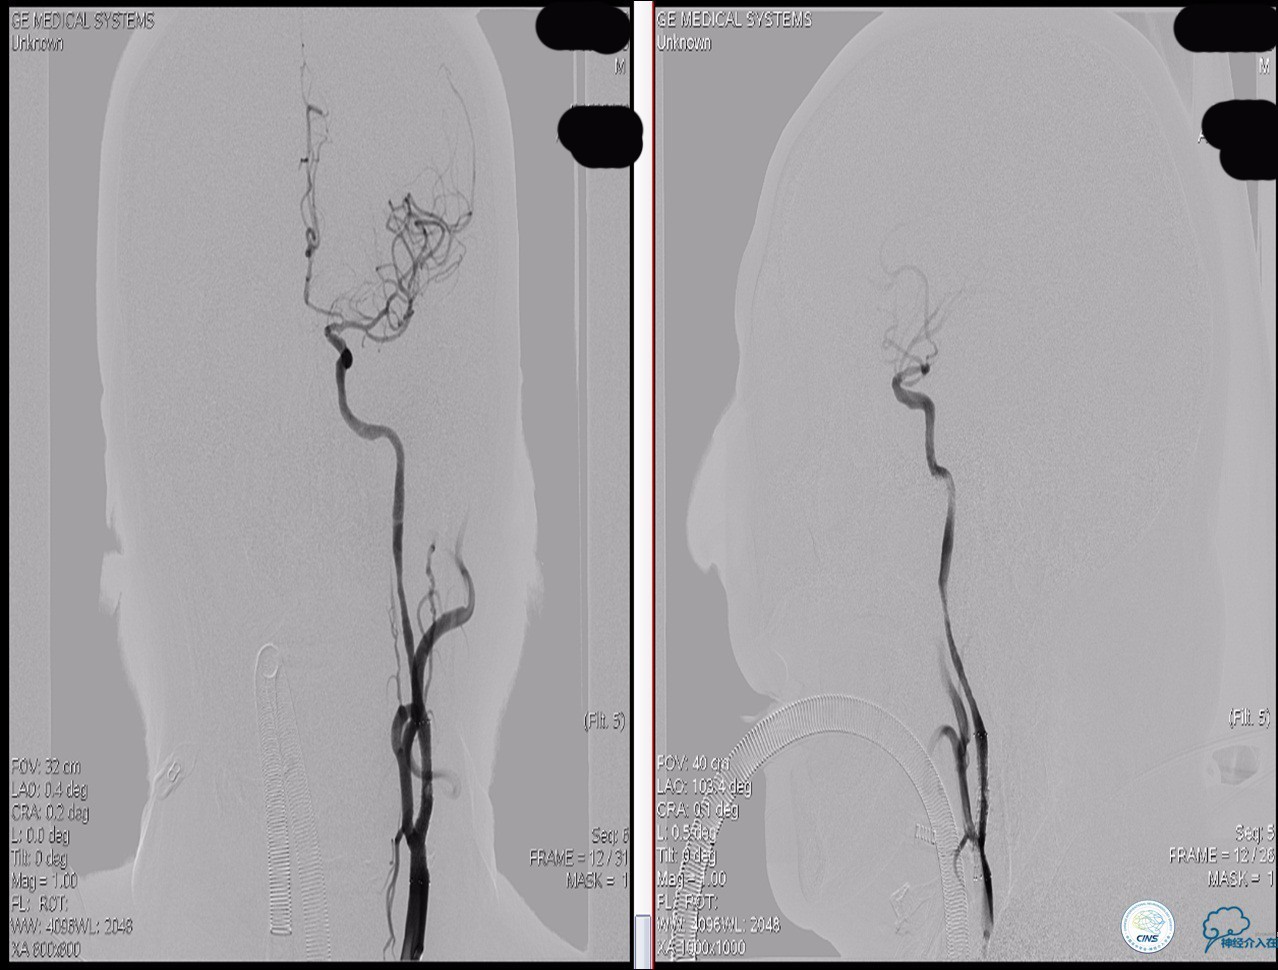

颈动脉次全闭塞 术前评估

》头颅灌注+DSA!

头颅灌注: 关注两侧CBF CBV的对比。

DSA:关注侧支代偿。

》当成颈动脉闭塞开通做,同时8F鞘内套以4F鞘给予微导管足够支撑力。

》避免后扩,分次治疗。

》术中脑保护,首选SPIDER。

★脑保护技术:病死率及卒中率从7.9%~9.1%降至1.7%,已作为CAS治疗常规。